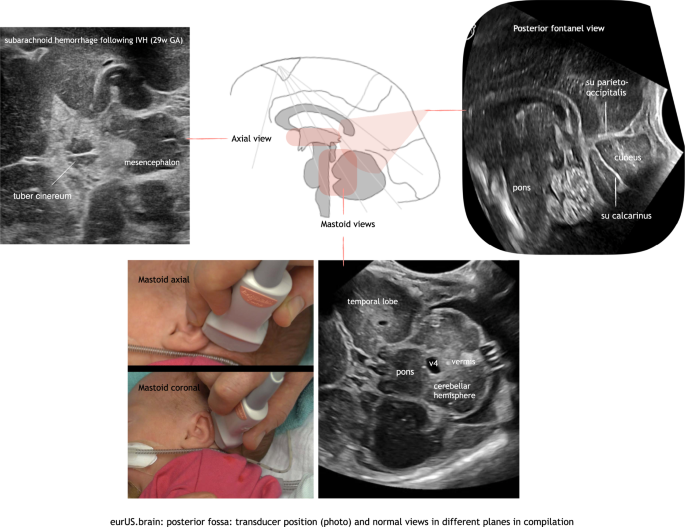

The mastoid fontanel

Several articles have recommended imaging through the mastoid fontanel (MF), also referred to as posterolateral fontanel, to improve ultrasound imaging of the neonatal posterior fossa.9,10,11 With this approach the transducer is placed closer to the posterior fossa structures. Therefore, higher transducer frequencies can be used (8–11 MHz with the standard microconvex probes and even higher, up to 15–18 MHz, with linear probes), thus improving the resolution of the images. Furthermore, the structures are approached from underneath the tentorium and at a more perpendicular angle instead of parallel to the ultrasound beam. This leads to a better visualization of the posterior fossa structures and to a better detection of abnormalities.12,13,14 The MFs are located at the junction of the parietal, temporal, and occipital bones8,9,10,11,15 When performing the examination, the sonographist places the transducer in the mastoid area, behind the helix of the ear and then slightly moves and rotates it to obtain a clear and symmetric view of the posterior fossa. Images are recorded in axial (also transverse) and coronal planes, at different levels.9,10 Cerebellar hemispheres, cerebellar vermis, cisterna magna, the fourth ventricle, and its plexus can be easily visualized through the MF.9,10,16 In addition, the transcerebellar diameter can be measured. The use of color Doppler allows visualization of venous flow in the transverse and sigmoid sinuses: this can be useful in the diagnosis of sinovenous thrombosis.17,18 In our experience, neonates can show some signs of discomfort during MF sonography. This may be explained by an auditory response to pulses of radiofrequency energy.19 Therefore, we advise to perform these views at the end of the CUS examination. Often the whole posterior fossa can be scanned through one single side MF (the one most easily accessible). The opposite MF can be used to confirm or exclude any suspected abnormalities, during the same or a subsequent examination. Usually the approach only costs a few minutes of additional scanning time.

The posterior fontanel

The posterior fontanel (PF) is located at the junction of the lambdoid and sagittal sutures.11,15 PF CUS is especially useful in the diagnosis of low-grade germinal matrix-intraventricular hemorrhage (GMH-IVH) and lesions in the occipital parenchyma, and also helps to define posterior fossa anatomy.20 PF CUS includes both coronal and sagittal views. Especially the midsagittal section provides a more detailed view of the cerebellar vermis, fourth ventricle, and cisterna magna (Figs. 2 and 3).